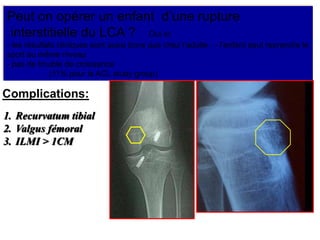

Peut on opérer un enfant d’une rupture

interstitielle du LCA ? Oui si:

- les résultats cliniques sont aussi bons que chez l’adulte - - l’enfant peut reprendre le

sport au même niveau

- pas de trouble de croissance

(11% pour le ACL study group)

Complications:

1. Recurvatum tibial

2. Valgus fémoral

3. ILMI > 1CM